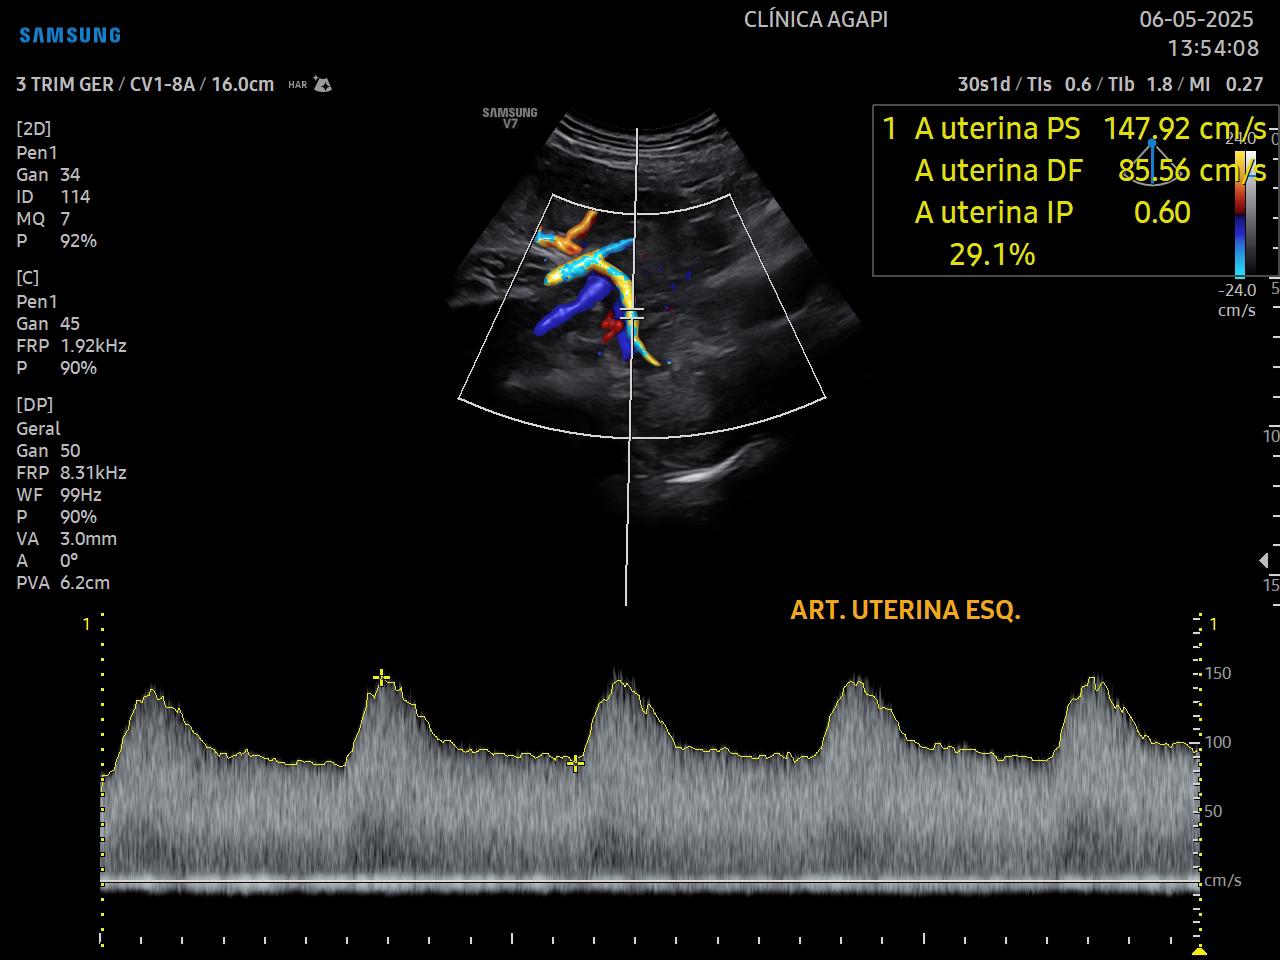

O doppler materno inclui a avaliação das artérias uterinas e o doppler fetal: artéria umbilical, artéria cerebral média, relação cérebro-placentária e quando necessário, ducto venoso.

A função do doppler é avaliar a vitalidade fetal e a função placentária.